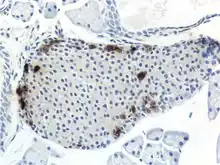

A pancreatic islet from a mouse in a typical position, close to a blood vessel; insulin in red, nuclei in blue.